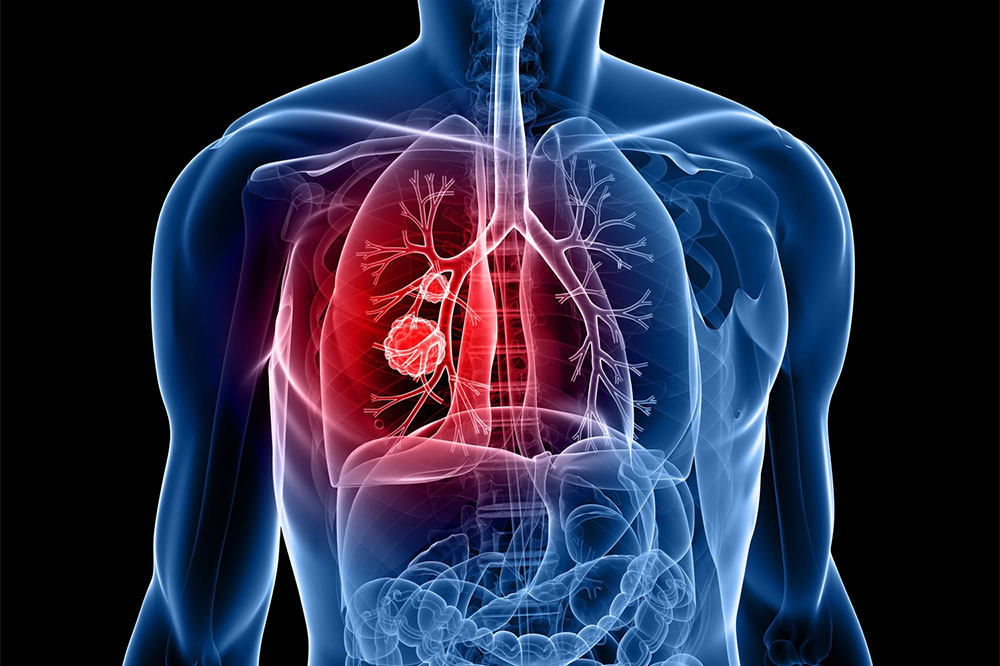

Lung cancer is among the most common causes of cancer-related deaths in our country. While smoking and an unhealthy lifestyle are the major risk factors associated with lung cancer, the disease can also result from breathing poor quality air. Places with a lot of air pollution are therefore known to report more lung cancer cases. In this article, we have listed five cities that have the highest rates of lung cancer.